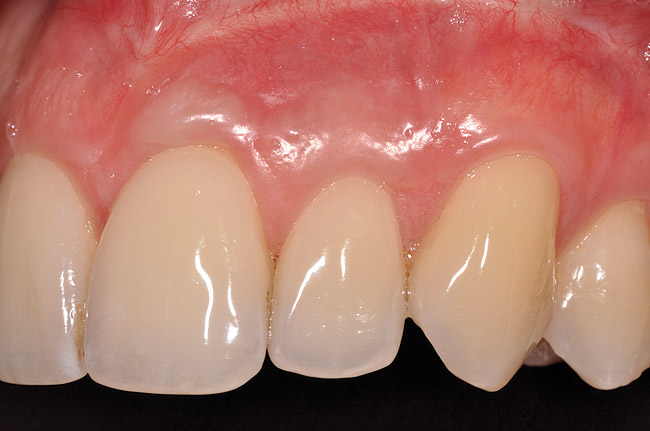

Once the flap was coronally repositioned and secured, a securing periosteal tac procedure was performed to prevent any micro movement superior to the mucogingival junction in the initial healing phase. A 4.0 chromic gut suture (Surgical Specialties Corp.) was used to engage the periosteum superior to the mucogingival junction and stabilize the tissues superior to the securing suture (Figure 12 and Figure 13). Multiple periosteal tac sutures may be necessary, depending on the size of the surgical field. Postoperatively, the periosteal tac sutures are routinely removed if not totally absorbed at 7 days; the flap sutures are removed at 2 to 3 weeks, and dermal-securing sutures are removed 1 month after surgery. The 1-year post-treatment clinical view shown in Figure 14 depicts the excellent soft-tissue result, band of attached keratinized tissue present, and excellent color match to the host gingival tissues.

Fig 14. One-year postoperative view of case presented.

Figure 14